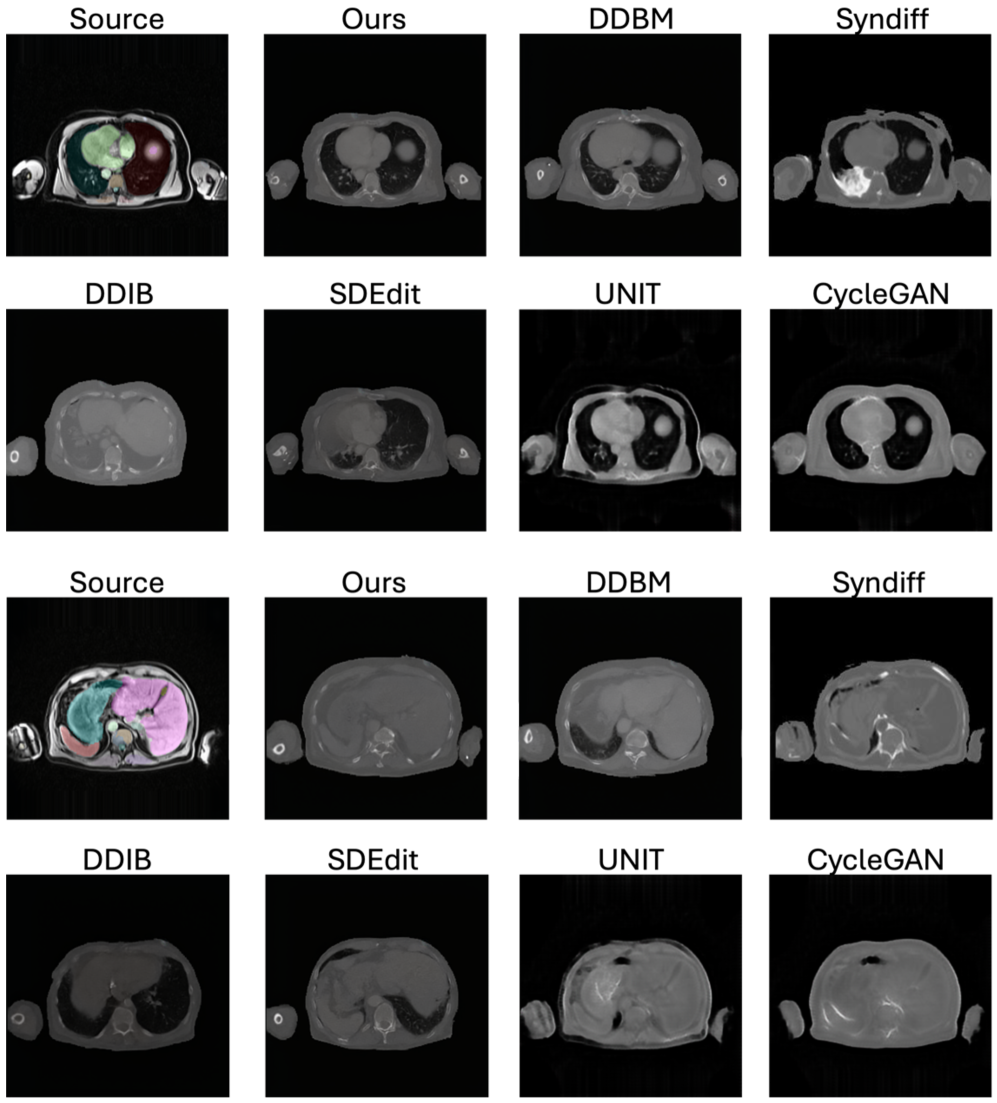

Refer to caption

Figure 4: Our SSB ensures anatomically consistent MRI\rightarrowCT translation across in-domain and out-of-domain scenarios. Segmentation masks are overlaid on MRI source images in OOD settings to provide structural reference, as paired CT ground truth is unavailable. They are not used during training or inference and serve only to illustrate anatomical fidelity without segmentation supervision.

We compare our method against representative baselines widely used in medical I2I translation, including GAN-based models CycleGAN Zhu et al. (2017) and UNIT Liu et al. (2017), zero-shot diffusion approaches SDEdit Meng et al. (2022) and DDIB Su et al. (2023), and the hybrid CycleGAN–diffusion framework SynDiff Özbey et al. (2023a). Since edge-based representations, such as Canny edges, are commonly used in MRI–CT translation—where diffusion models learn to reconstruct images from edge maps in a self-supervised manner Chen et al. (2024)—we additionally implement a DDBM variant using Canny edges. This comparison demonstrates that DINO-based embeddings capture richer geometric and semantic information than handcrafted edge filters. Fig. 4 and Table 1 present qualitative and quantitative results on in-domain and OOD MRI\rightarrowCT translation. Since no paired CT is available, we compute FID against CT scans from the training set and MS-SSIM between the input MRI and the synthesized CT as a proxy for structural similarity. We also provide qualitative results and segmentation overlays, with additional visuals in the Appendix. Our method shows stronger robustness to new MRI contrasts and achieves more accurate translations than SynDiff and DDBM, preserving geometry and modality realism.